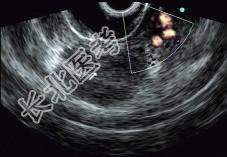

- 单项选择题男性,50岁, 上腹隐痛,食欲不振3个月。1个月来出现黄疸且进行性加深, 体重明显减轻,查体全身明显黄染, 肝未触及,深吸气时可触到肿大胆囊底部, 无触痛。化验血胆红素15mg/dl,尿检胆红素阳性图中胰腺病变可能的诊断是 ( )

E、胰腺癌